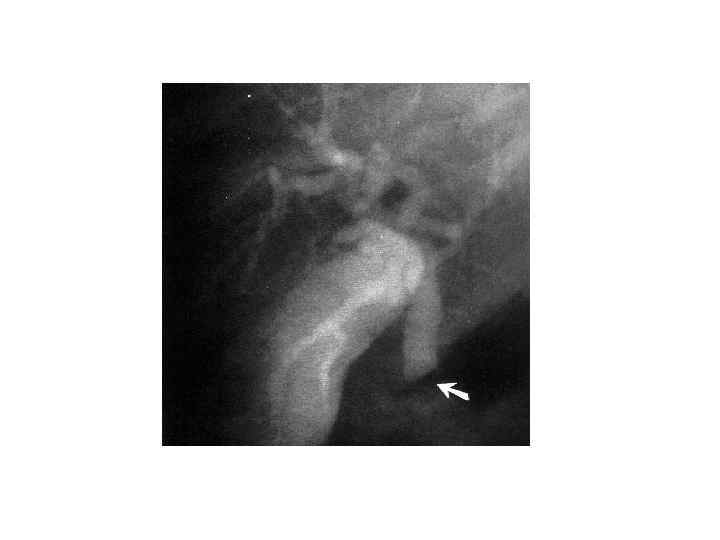

Диагностика • • • Сбор анамнеза Осмотр Обследование передней брюшной стенки Люборатоные данные: общий анализ крови; биохимическое исследование крови, Дуоденальное зоондирование с бактериологическим исследованием всех порций желчи Рентгенологическое исследование УЗИ КТ РХПГ ФЭГДС Лапароскопия радиоизотопное исследование

Диагностика • • • Сбор анамнеза Осмотр Обследование передней брюшной стенки Люборатоные данные: общий анализ крови; биохимическое исследование крови, Дуоденальное зоондирование с бактериологическим исследованием всех порций желчи Рентгенологическое исследование УЗИ КТ РХПГ ФЭГДС Лапароскопия радиоизотопное исследование